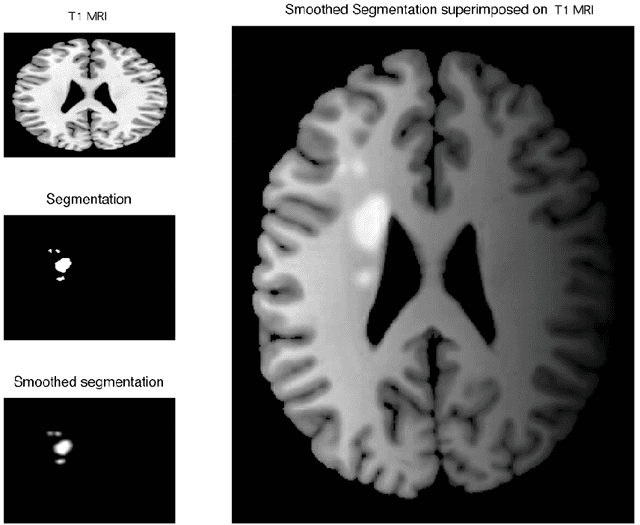

Abstract:Image acquisition and segmentation are likely to introduce noise. Further image processing such as image registration and parameterization can introduce additional noise. It is thus imperative to reduce noise measurements and boost signal. In order to increase the signal-to-noise ratio (SNR) and smoothness of data required for the subsequent random field theory based statistical inference, some type of smoothing is necessary. Among many image smoothing methods, Gaussian kernel smoothing has emerged as a de facto smoothing technique among brain imaging researchers due to its simplicity in numerical implementation. Gaussian kernel smoothing also increases statistical sensitivity and statistical power as well as Gausianness. Gaussian kernel smoothing can be viewed as weighted averaging of voxel values. Then from the central limit theorem, the weighted average should be more Gaussian.